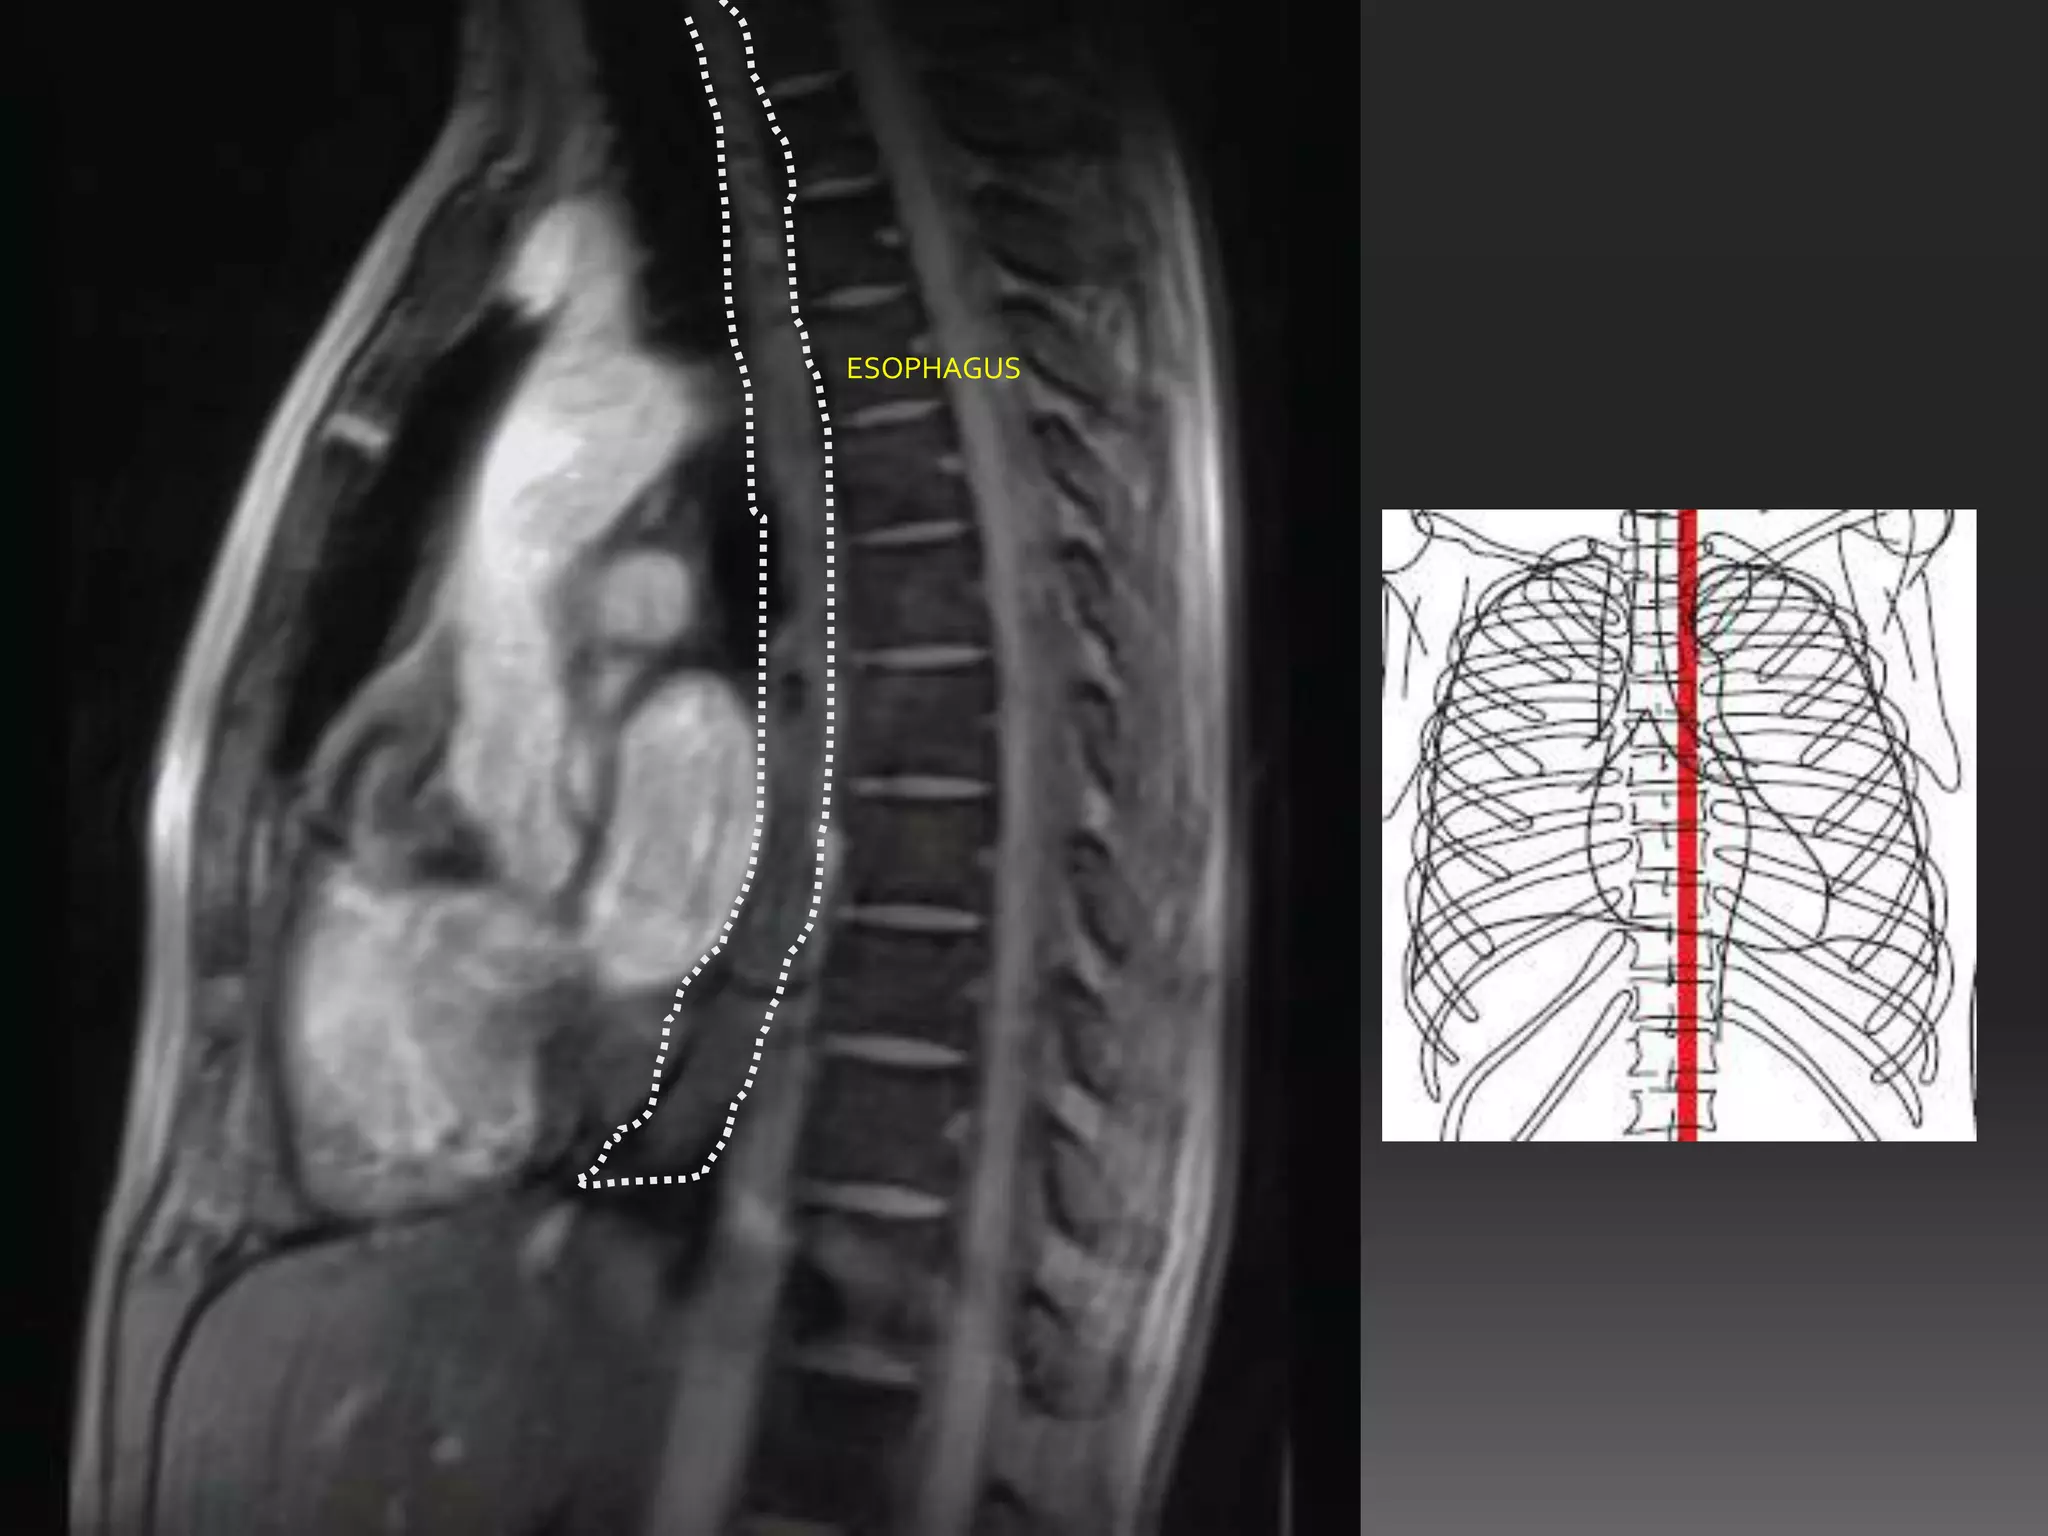

ESOPHAGUS

ESOPHAGUES